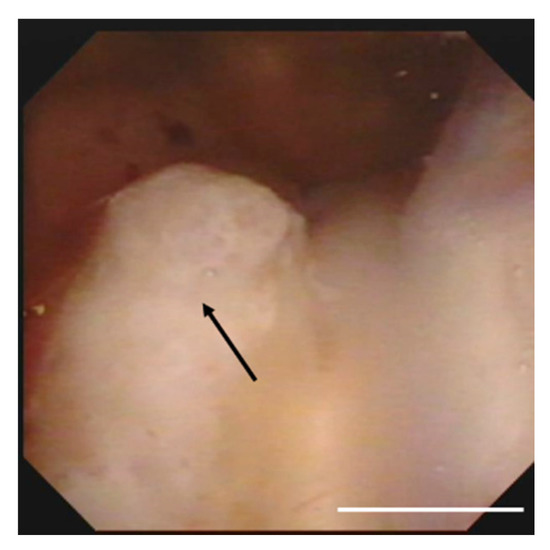

Total body imaging and bone marrow aspirate histology displayed no evidence of systemic disease. Lumbar puncture was performed, and CSF analysis showed atypical lymphocyte infiltration. Microbiological studies for bacterial, mycobacterial or fungal infections were negative. On day 5, she was in altered sensorium, drowsy and disoriented, and this manifested in a loss of consciousness on day eight. A disturbance of consciousness occurred due to the progression of hydrocephalus, for which a ventricular drainage was performed. Ventricular inspection using neuro endoscopy identified the presence of a tumoral mass in the lateral ventricle, and a biopsy was taken for diagnosis (Figure 3).

Figure 3. Operative findings showing a solid tumor (arrows) in the right lateral ventricle densely adherent to the choroid plexus. Scale bar, 1 cm.